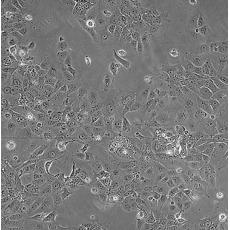

HCC827

中文名稱 人非小細胞肺癌細胞

組織來源 肺腺癌;女性

生長特性 adherent

培養基 RPMI-1640+10% FBS+1% P/S

形態特征 epithelial

細胞描述 This lung adenocarcinoma has an acquired mutation in the EGFR tyrosine kinase domain(E746-A750 deletion).